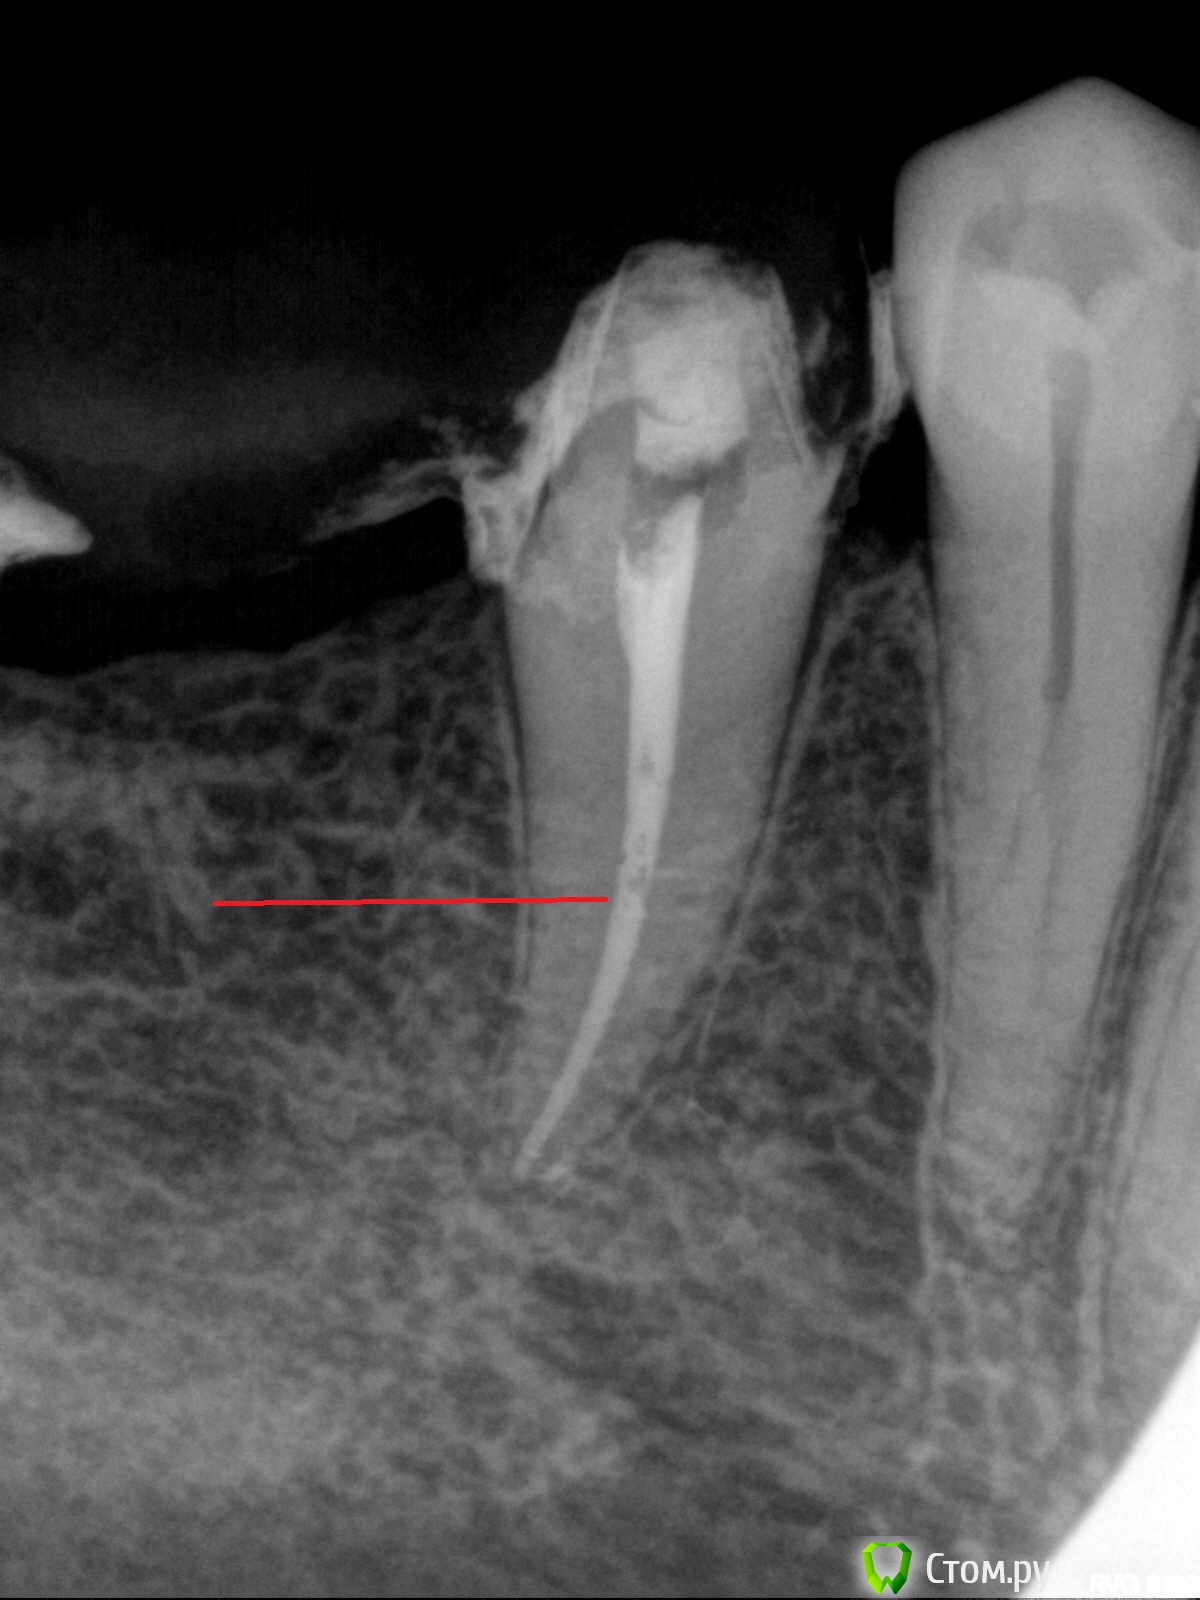

sorriso Опубликовано 3 июля, 2014 Поделиться Опубликовано 3 июля, 2014 (изменено) Вытягивается вместе с плагером? Или , наоборот, не обрезается? Обрезается, но прилипает к стенкам?Я думаю,что не обрезается,а возможно и обрезается,но прилипает к стенкам. То,что я отожгла,не выходит с плагером, а квасится внутри. И получается вот такое Выше красной черты то,что не удалось отжечь Изменено 3 июля, 2014 пользователем sorriso Ссылка на комментарий

Мартовский Опубликовано 3 июля, 2014 Поделиться Опубликовано 3 июля, 2014 Я думаю,что не обрезается,а возможно и обрезается,но прилипает к стенкам. То,что я отожгла,не выходит с плагером, а квасится внутри. И получается вот такое R5.jpg Выше красной черты то,что не удалось отжечьЕсть такой способ - отожгли, не вытаскивая паяльник считаем до десяти, потом на секунду отожгли еще, и вытащили. Ссылка на комментарий

Л Ю С Я Опубликовано 4 июля, 2014 Поделиться Опубликовано 4 июля, 2014 Думаю плагер может быть неправильно подобран - слишком тонкий. Попробуй еще температуру увеличить. У бифила есть болезнь: отходят плагер и не нагревается, всегда проверяю на гуттаперче , прежде чем ввести в канал, замучилась с ним. На снимке наверное поры между 1 и 2 частью, это ведь волна? Ссылка на комментарий

sorriso Опубликовано 7 июля, 2014 Поделиться Опубликовано 7 июля, 2014 Думаю плагер может быть неправильно подобран - слишком тонкий. Попробуй еще температуру увеличить. У бифила есть болезнь: отходят плагер и не нагревается, всегда проверяю на гуттаперче , прежде чем ввести в канал, замучилась с ним. На снимке наверное поры между 1 и 2 частью, это ведь волна?Температуру выставляю от 160 до 200. Да это волна,а место между 1 и 2 частью это как раз место,где не отожглась гуттаперча Ссылка на комментарий